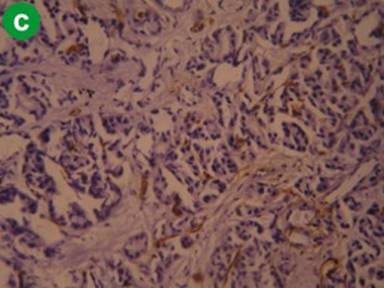

Normal Pancreas

Tissues were included for study in normal pancreas group based on normal looking pancreas in H&E stained sections (Figure 4a). Immunohistochemistry with α-SMA showed scattered and sparse staining only in vast majority of cases. However, in some cases slightly increased positivity was noted. Positive staining was mainly in the wall of vessels and ducts (Figure 4b). Staining with CD34 generally showed more positivity than with α-SMA, and stained areas tended to delineate blood vessels and ducts (Figure 4c). These observations suggest that there is no, or only negligible, amount of activated stellate cells in normal pancreas.

Figure 4. Representative staining pattern observed in cases of normal pancreas (a. H&E, b. α-SMA, c. CD34). |